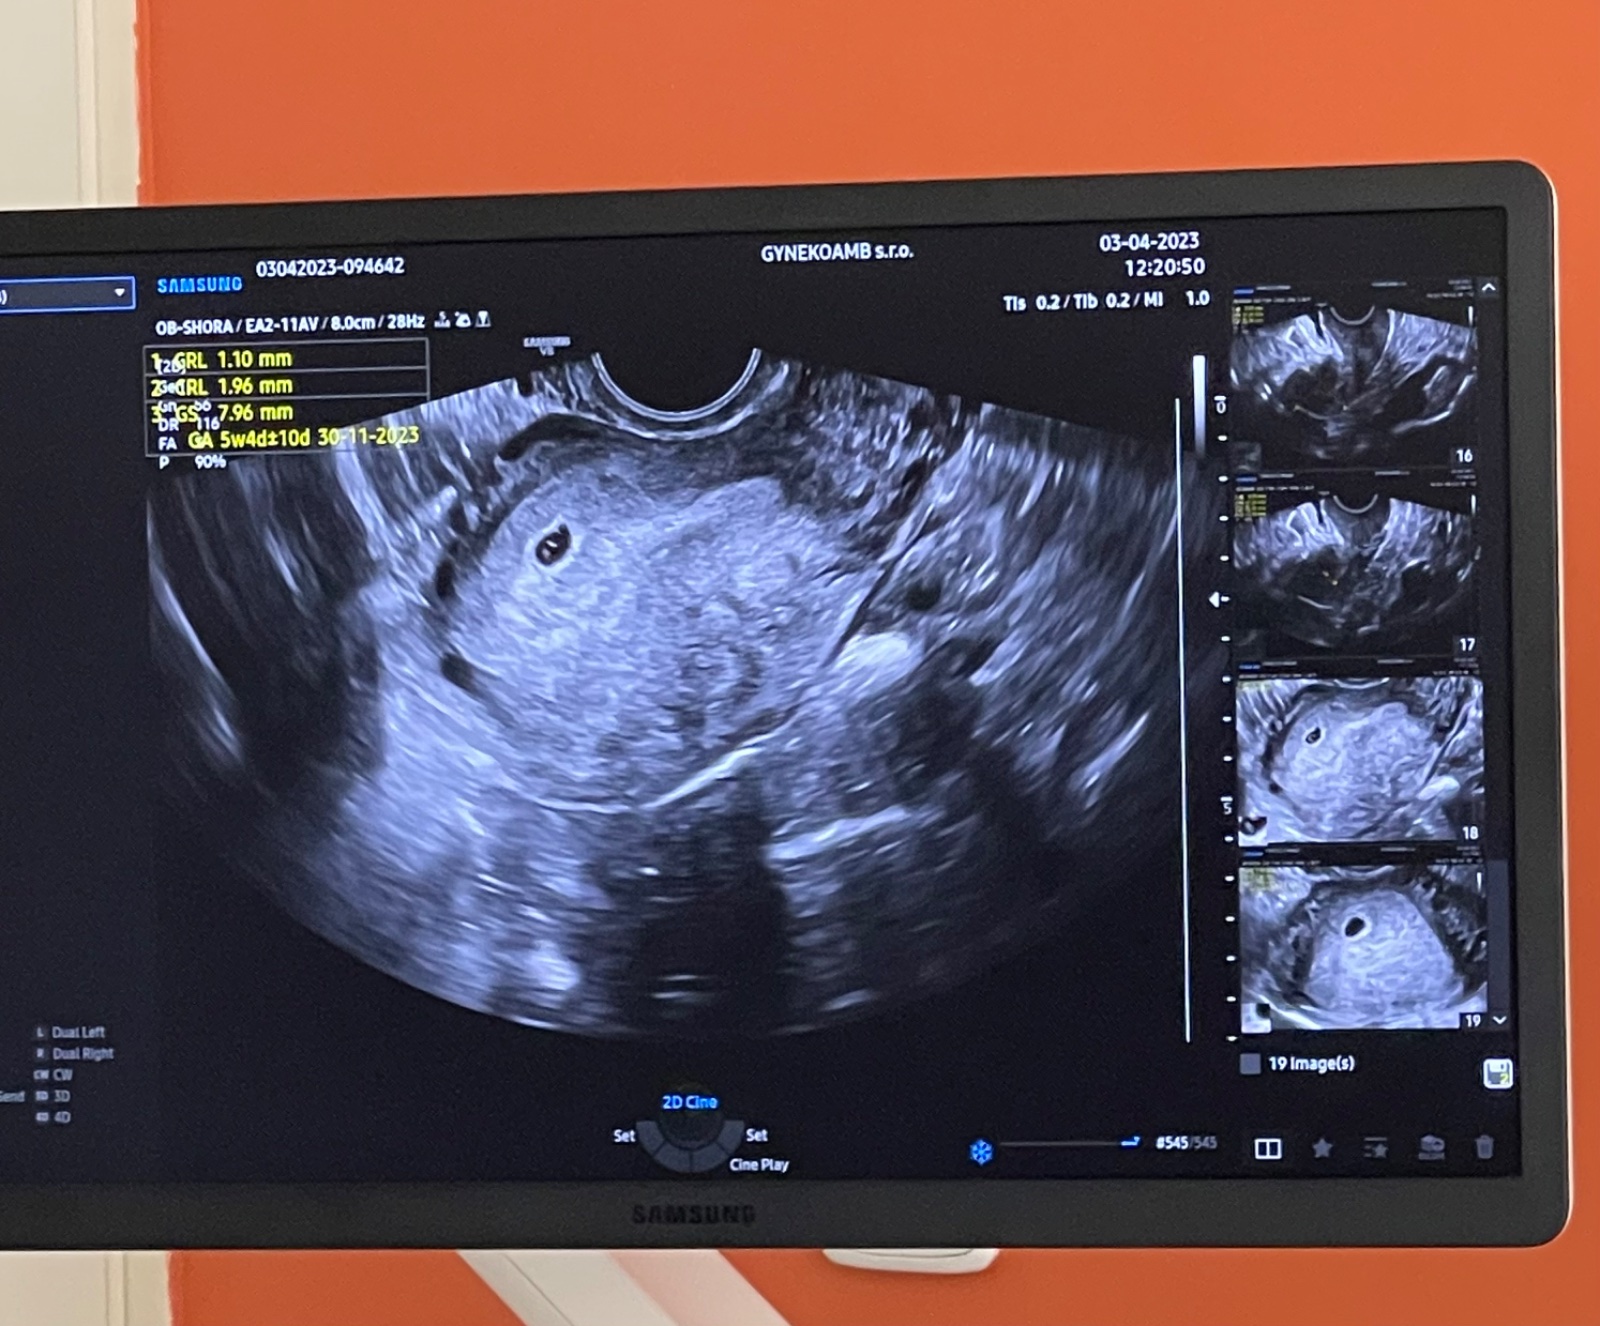

chtěla bych se zeptat, jestli na ultrazvuku je vše v pořádku - hodnota hCG v pondělí byla 3500.

Dle utz jsem nyní 5+6tt.

Jsou ty hodnoty dle ultrazvuku v pořádku?

ano, co lze vidět z obrázku a z toho, co píšete, na ultrazvuku bylo vidět nejspíše nitroděložní těhotenství a drobný embryonální pól. Hodnota hCG tomu odpovídá. Nepíšete, zda již byla vidět srdeční akce, ale pokud ne, tak při takto časné graviditě to ultrazvuk ještě vidět nemusí. Je na místě kontrola s odstupem, jak máte plánováno k potvrzení růstu těhotenství a přítomnosti srdeční akce.

Ještě doplním, teď jsem si všiml, že jste se ptala už před pár dny ke stejnému snímku ohledně toho, zda v děloze nejsou dva zárodky (2x CRL). K tomu se ze statického malého snímku nelze vůbec vyjádřit, vyšetření v reálném čase snímek nenahradí.